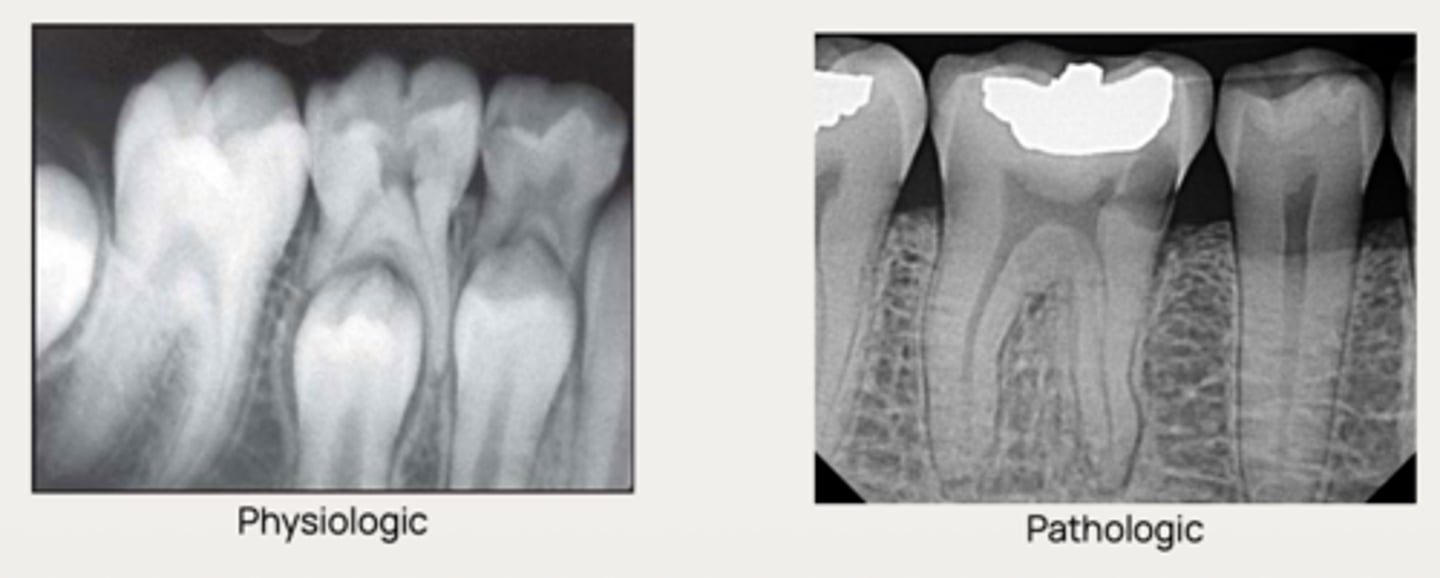

What is a condition associated with either a physiologic or a pathologic process resulting in a loss of dentin, cementum and/or bone?

Physiologic resorption

What type of resorption allows the permanent successor tooth to erupt?

How are dental resorptive lesions classified?